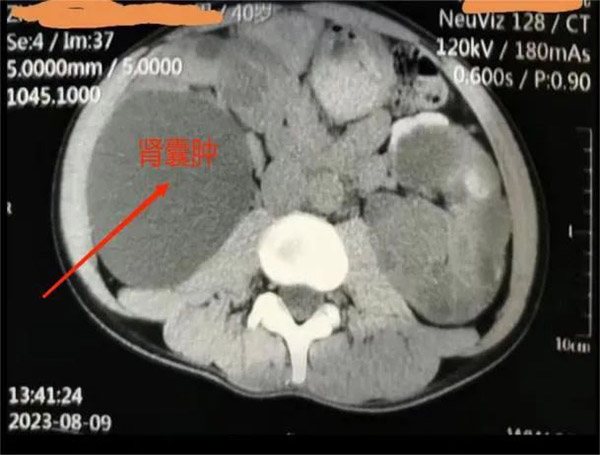

▲患者肾囊肿影像

肾内科主任洪敏接诊后,对王先生进行了详细的检查,结合其病情和身体情况,决定实施超声引导下经皮穿刺抽液囊肿硬化治疗。

“超声引导下经皮穿刺抽液硬化治疗能清晰显示囊肿的位置、大小、深度以及和周围脏器的关系,实时观察穿刺治疗过程,操作简便、安全,无辐射,更适合不愿接受外科手术的王先生。”洪敏主任表示。